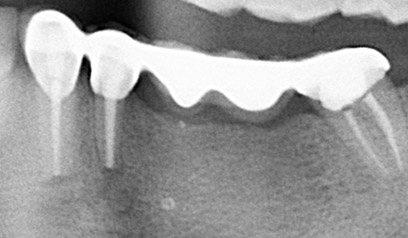

Oft kann eine Wurzelspitzenresektion nach erfolgloser Wurzelbehandlung als letzte Möglichkeit angesehen werden, einen Zahn noch so lange wie möglich im Kieferknochen zu behalten.

Hierbei wird ein chirurgischer Zugang zu der Spitze der Zahnwurzel erstellt. Als nächster Schritt wird die Wurzelspitze reseziert, das entzündete Gewebe entfernt und dicht verschlossen. Im günstigsten Fall wird so ein oft fraglicher Zahn wieder erhaltungswürdig.